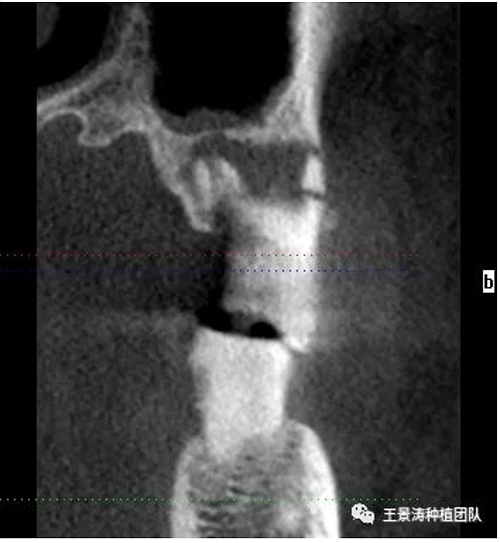

患者左側(cè)16慢性根尖周炎,17缺失。16根尖炎癥距上頜竇底較近,需內(nèi)提升,但是因?yàn)閮?nèi)提升后骨質(zhì)較薄所致植入深度過深,埋入式植入。17非埋入式種植。后期效果均可。

術(shù)后一周

二期手術(shù)